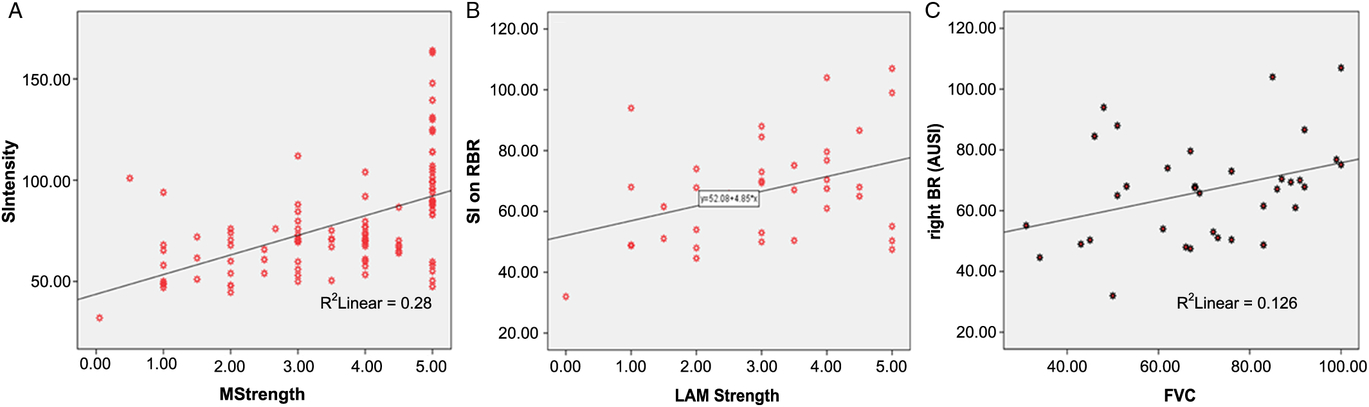

In the whole cohort, 34 subjects (33 patients and 1 control subject) exhibited the BR sign in the posterior bank of the motor cortex. A quantitative analysis confirmed that patients with ALS had significantly higher paramagnetic effect in this region, and a receiver operating characteristic analysis indicated that a cut-off value of 83 AUSI in the posterior bank of the motor cortex had an AUC of 0.95 (p < 0.001) for discriminating patients with ALS from control subjects. Additionally, there was a reliable correlation between muscle strength in the contralateral upper extremities and signal intensity of the BR (Figure 4A). Respiratory forced vital capacity and body mass index showed significant relationships with signal attenuation in the BR area with a Pearson’s coefficient of 0.355 (p = 0.036) and 0.363 (p = 0.010), respectively. Patient-scored quality of life was only correlated with deterioration index (Pearson’s coefficient = 0.506, p = 0.002). There was a marginal correlation between measured BR area and body mass index (p = 0.044), while BR signal intensities in both precentral gyri were significantly correlated with forced vital capacity (Spearman r = 0.380, p = 0.020, in the right hemisphere and r = 0.33, p = 0.047, in the left hemisphere).

Figure 4: (A) Relationship between signal intensity in the right black ribbon and muscle strength in the contralateral arm in all subjects. Pearson’s coefficient is 0.578 (p < 0.001). (B) Correlation between signal intensity in the right black ribbon and strength in the left arm in the ALS group. Spearman’ rho is 0.380 (p = 0.020). (C) Relationship between signal intensity in the right black ribbon and forced vital capacity Spearman’ rho is 0.376 (p = 0.026).